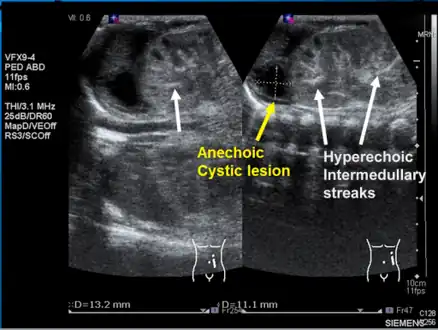

-

Left kidney with a suprarenal anechoic cyst-like lesion and hyperechoic intermedullary streaks in initial phase of renal vein thrombosis -

Observing the patient's symptoms, medical history and imaging remain the fundamental source for diagnosing RVT. Imaging is used to detect the presence of a blood clot. In an abnormal kidney with RVT, a blood clot is present in the renal vein. In cases where the renal vein is suddenly and/or fully blocked, the kidneys will enlarge, reaching its maximum size within a week. An ultrasound imaging can be used to observe and track the size of the kidneys in RVT patients. Ultrasound is not efficient for use in detecting blood flow in the renal veins and artery. Instead a color doppler ultrasound may be used to detect renal blood flow. It is most commonly used to detect RVT in patients who have undergone renal transplantation. CT angiography is currently the top choice in diagnosing RVT. It is non-invasive, relatively cheap and fast with high accuracy. CT scanning can be used to detect renal enlargement, renal tumors, blood flow and other renal pathologies. An alternative is magnetic resonance angiography or MRA. It is non-invasive, fast and avoids radiation (unlike a CT scan) but it is relatively expensive. MRA produces detailed images of the renal blood flow, vesicle walls, the kidneys and any surrounding tissue. An inferior venocavography with selective venography can be used to rule out the diagnoses of RVT.[6]